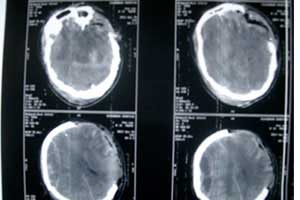

3.脑外伤后癫痫:外伤后癫痫是指脑外伤以后发生的癫痫。癫痫发作是由于大脑神经元的异常放电引起,10 %的严重脑非贯通伤和40%脑贯通伤患者发生癫痫,可以在脑外伤后数年才出现。发作类型与异常放电起源的部位有关。点击咨询医师

5.脑外伤所致硬膜下血肿:可在受伤后很快发生,常见头痛和嗜睡。偶尔伴有谵妄性运动性兴奋,约半数病人有视乳头水肿。慢性硬膜下血肿的特点是嗜睡,迟钝,记忆减退,严重者出现全面性痴呆症状,部分病人脑脊液压力轻度升高,蛋白定量增加,外观呈黄色。点击咨询医师